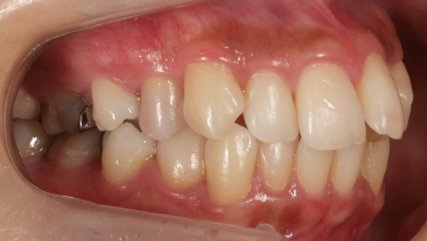

治療前

治療終了前

乱ぐい歯、でこぼこがとても酷い状態になります。歯が前後的に重なってしまっている、八重歯になっているなどがこのジャンルに入ります。

顎の大きさと歯の大きさのギャップが大きく、時には歯を抜かないと矯正治療ができない場合もあります。当院では治療期間が長くなるが抜かない治療方針など、一つの治療プランだけでなく、さまざまな可能性の治療方針を説明させて頂くよう心掛けております。こういった考え方はインフォームド・チョイスと言われ近年大切にされている考え方と言われております。